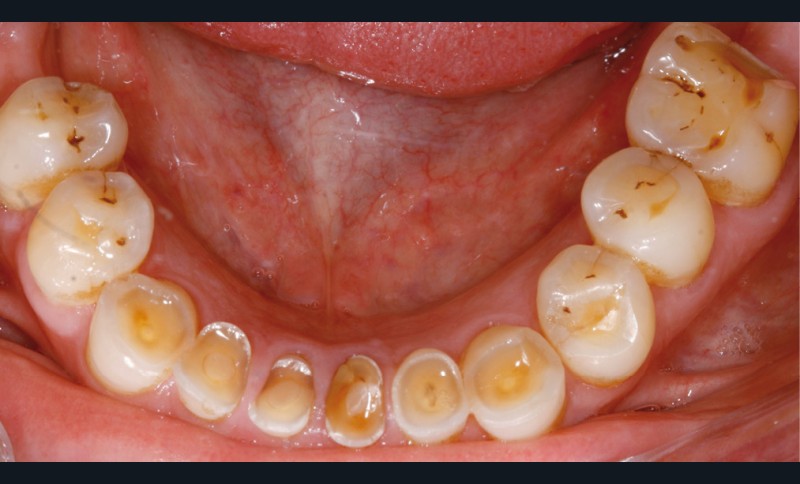

Un patient de 68 ans arrive au cabinet ; il présente de nombreux édentements ainsi qu’une usure parafonctionnelle très avancée.

Examen clinique (fig. 1-6)

• L’examen intrabuccal montre de nombreux édentements non compensés (14, 15, 16, 24, 25, 26, 27, 47 et 36) ainsi que des pertes de substance très importantes, notamment dans le secteur antérieur.

Une attrition sévère, couplée à une occlusion sans calage postérieur, a engendré des difficultés pour s’alimenter.

– perte de substance extrême du bloc incisivo-canin maxillaire et des incisives mandibulaires ;

– égressions compensatoires.